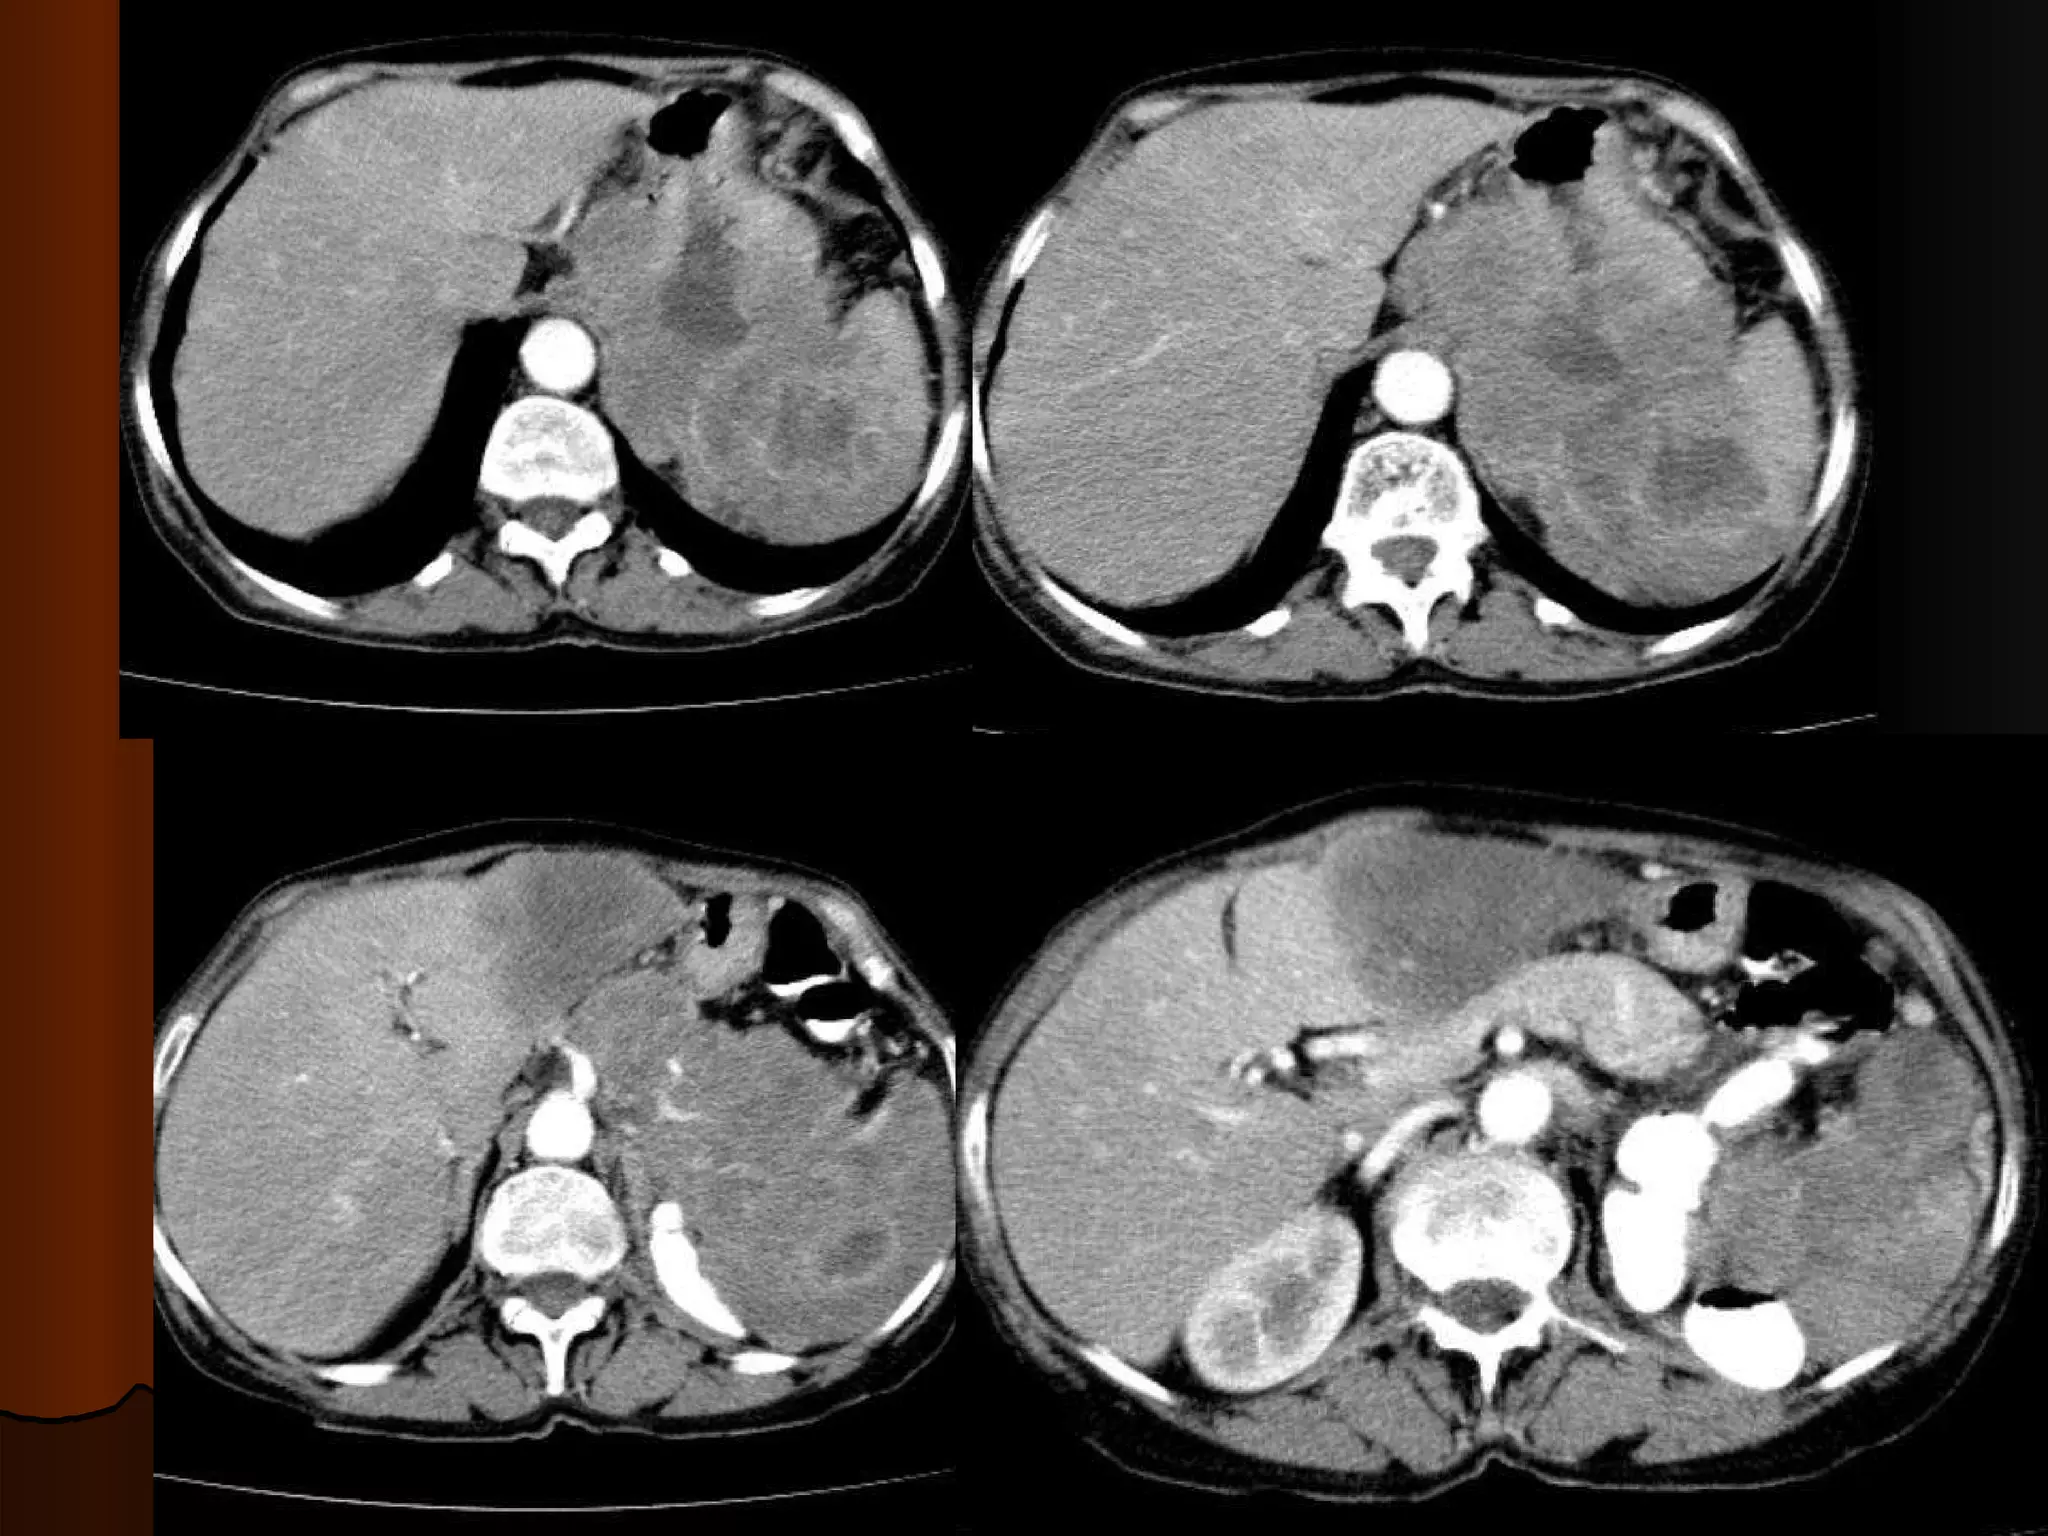

Случай 3. Различные КТ-находки в печени у одной молодой пациентки

Вопросы для дискуссии Какие фазы контрастирования представлены В чем их диагностическая ценность Характер усиления образований в печени Дифряд

Flash – гемангиомы Фибронодуляный гиперпластический узел Аденома?

Случай 3. РазличныеКТ-находки в печени у одной молодой пациентки

Вопросы для дискуссииКакие фазы контрастирования представлены В чем их диагностическая ценность Характер усиления образований в печени Дифряд

Flash – гемангиомыФибронодуляный гиперпластический узел Аденома?